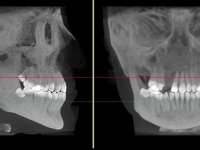

Root canal treatment was immediately performed on tooth 11. In the meanwhile, a CBCT scan was done to evaluate bone quality and quantity in the cleft area. The available bone was significantly reduced in vertical and horizontal dimensions. Due to the difficulty in performing a bone augmentation in this area, together with periodontal surgery to improve soft tissues, our treatment plan was the following: